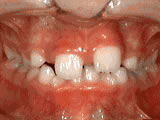

Spacing of teeth

Patient was bothered by the spaces between his teeth. Braces closed the spaces and gave him an ideal bite in 24 months. Special glued-in retainers help keep the spaces closed.